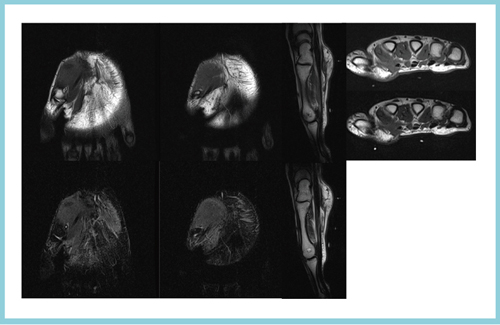

Open Bore 3T MRIと320列面検出器CTの最新臨床応用 Toshiba 3T

Open Bore 3T MRIと320列面検出器CTの最新臨床応用 Toshiba 3T